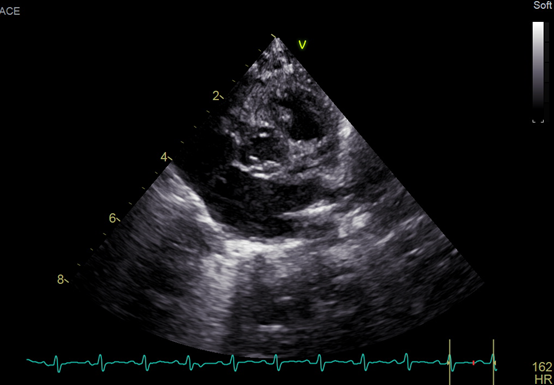

An echocardiogram showed a large ventricular septal defect overriding the aorta with septum and quadricuspid aortic valve (Figure). No stenosis or regurgitation was observed though the valve. The valve consisted of 3 equal cusps and a smaller one, which is type B according to the Hurwitz and Roberts classification (Video). Fluorescent in situ hybridization was negative for 22q11 deletion. The patient established feeds and was discharged home with the plan to have regular follow-ups.